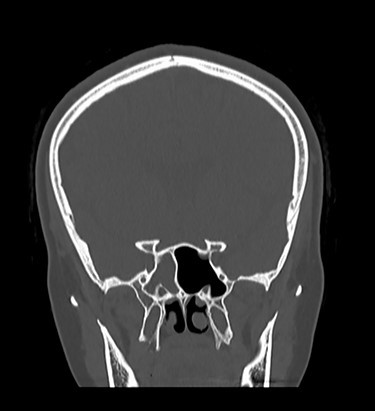

Patient underwent sinus computed tomography (CT), which demonstrated opacification of the right sphenoid sinus (Fig. 2). Brain MRI showed possible cerebrospinal fluid (CSF) leak at the right sphenoid sinus (Fig. 3). Lumbar puncture was done and fluid sent for analysis to rule out meningitis.

CT of paranasal sinuses, showing opacification of right sphenoid sinus.